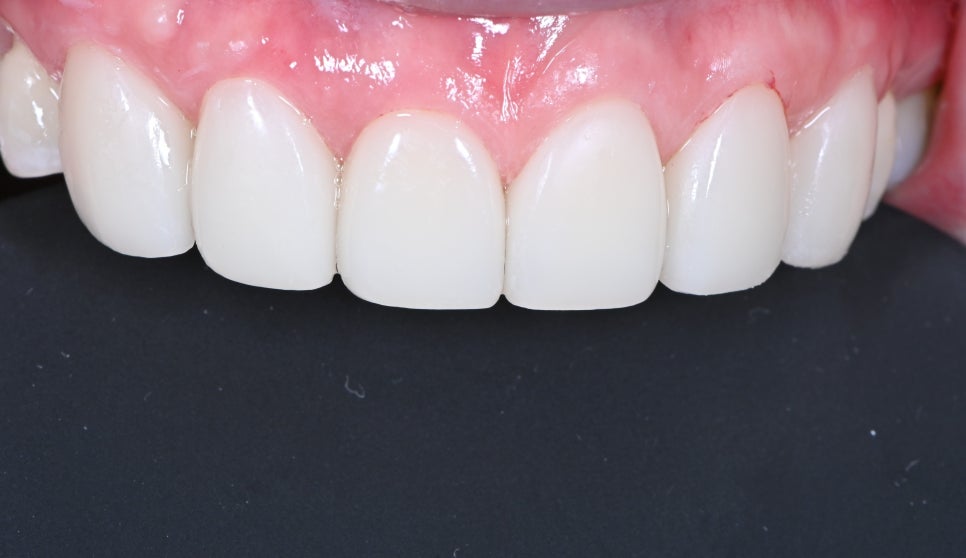

라미네이트 부착 후

스마일라인 변화

전후 사진입니다.

치료전에는 무의식적으로 신경 쓰이다 보니

웃는 모습이 자연스럽지 않지만

치료 후에는 자신 있게 입꼬리를 당겨서 웃게 되고

치아의 끝을 연결한 선이 아랫입술을 벗어나지 않는

이상적인 스마일 라인이 완성이 되었습니다.

인위적으로 웃는 모습을 만든다고 생각할 수 있지만

치아 형태가 바뀜에 따라 웃는 모습은

무의식적으로 환하게 웃게 되는 것을 확인할 수 있습니다